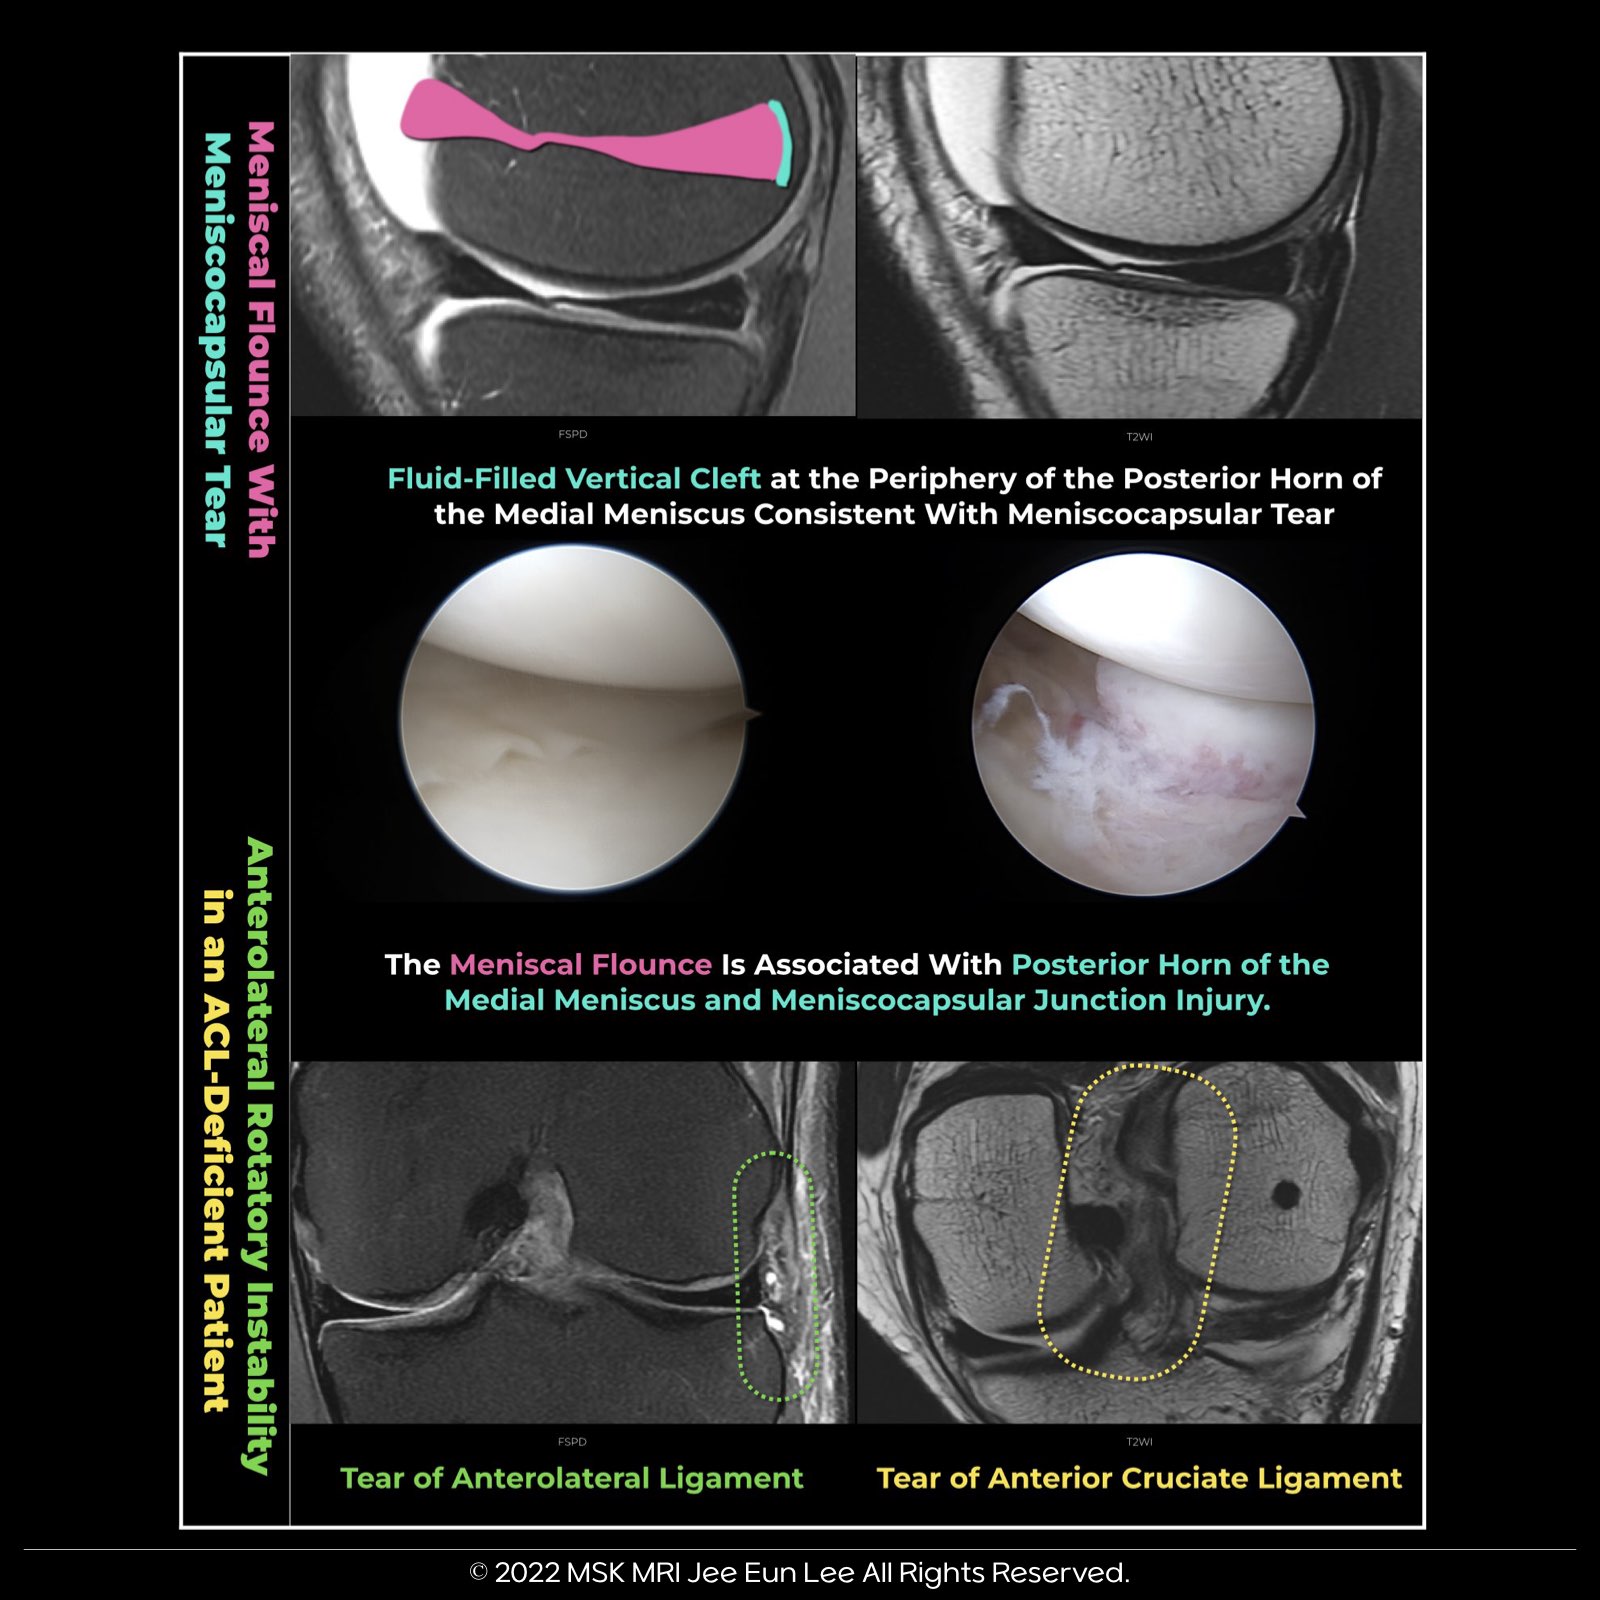

- The most significant factor linked to meniscal flounce is a tear at the posterior horn of the medial meniscus (PHMM), followed by a tear at the meniscocapsular junction.

- When meniscal flounce is observed on knee MRI, it's essential to perform a thorough evaluation to check for potential coexisting tears of the PHMM and the meniscocapsular junction.

- Meniscocapsular tears can lead to posterior meniscocapsular separation, resulting in the formation of a meniscal flounce.

- While the presence of meniscal flounce itself is not strongly associated with an increased incidence of meniscal tears, it should prompt careful assessment for possible ligamentous or capsular injuries.